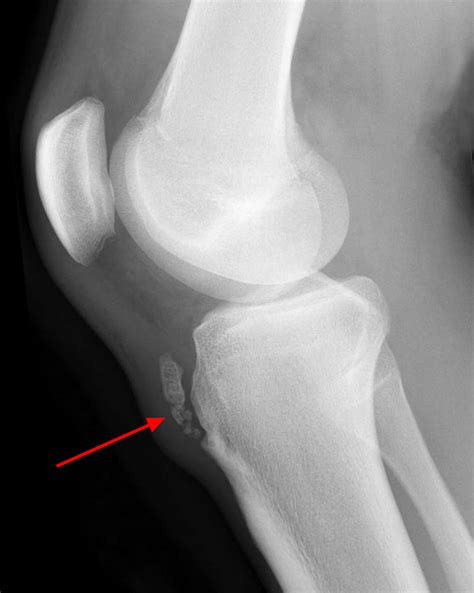

Diagnosing Osgood-Schlatter disease typically involves a physical examination and a review of the patient's medical history. The healthcare provider will ask about the symptoms, the onset of pain, and any recent changes in physical activity. They will also perform a physical examination to assess the affected knee, checking for tenderness, swelling, and any visible bumps.

In some cases, imaging tests such as X-rays, ultrasound, or MRI may be ordered to rule out other conditions and confirm the diagnosis. These tests can help visualize the tibial tuberosity and the patellar tendon, providing a clearer picture of the inflammation and any underlying issues.